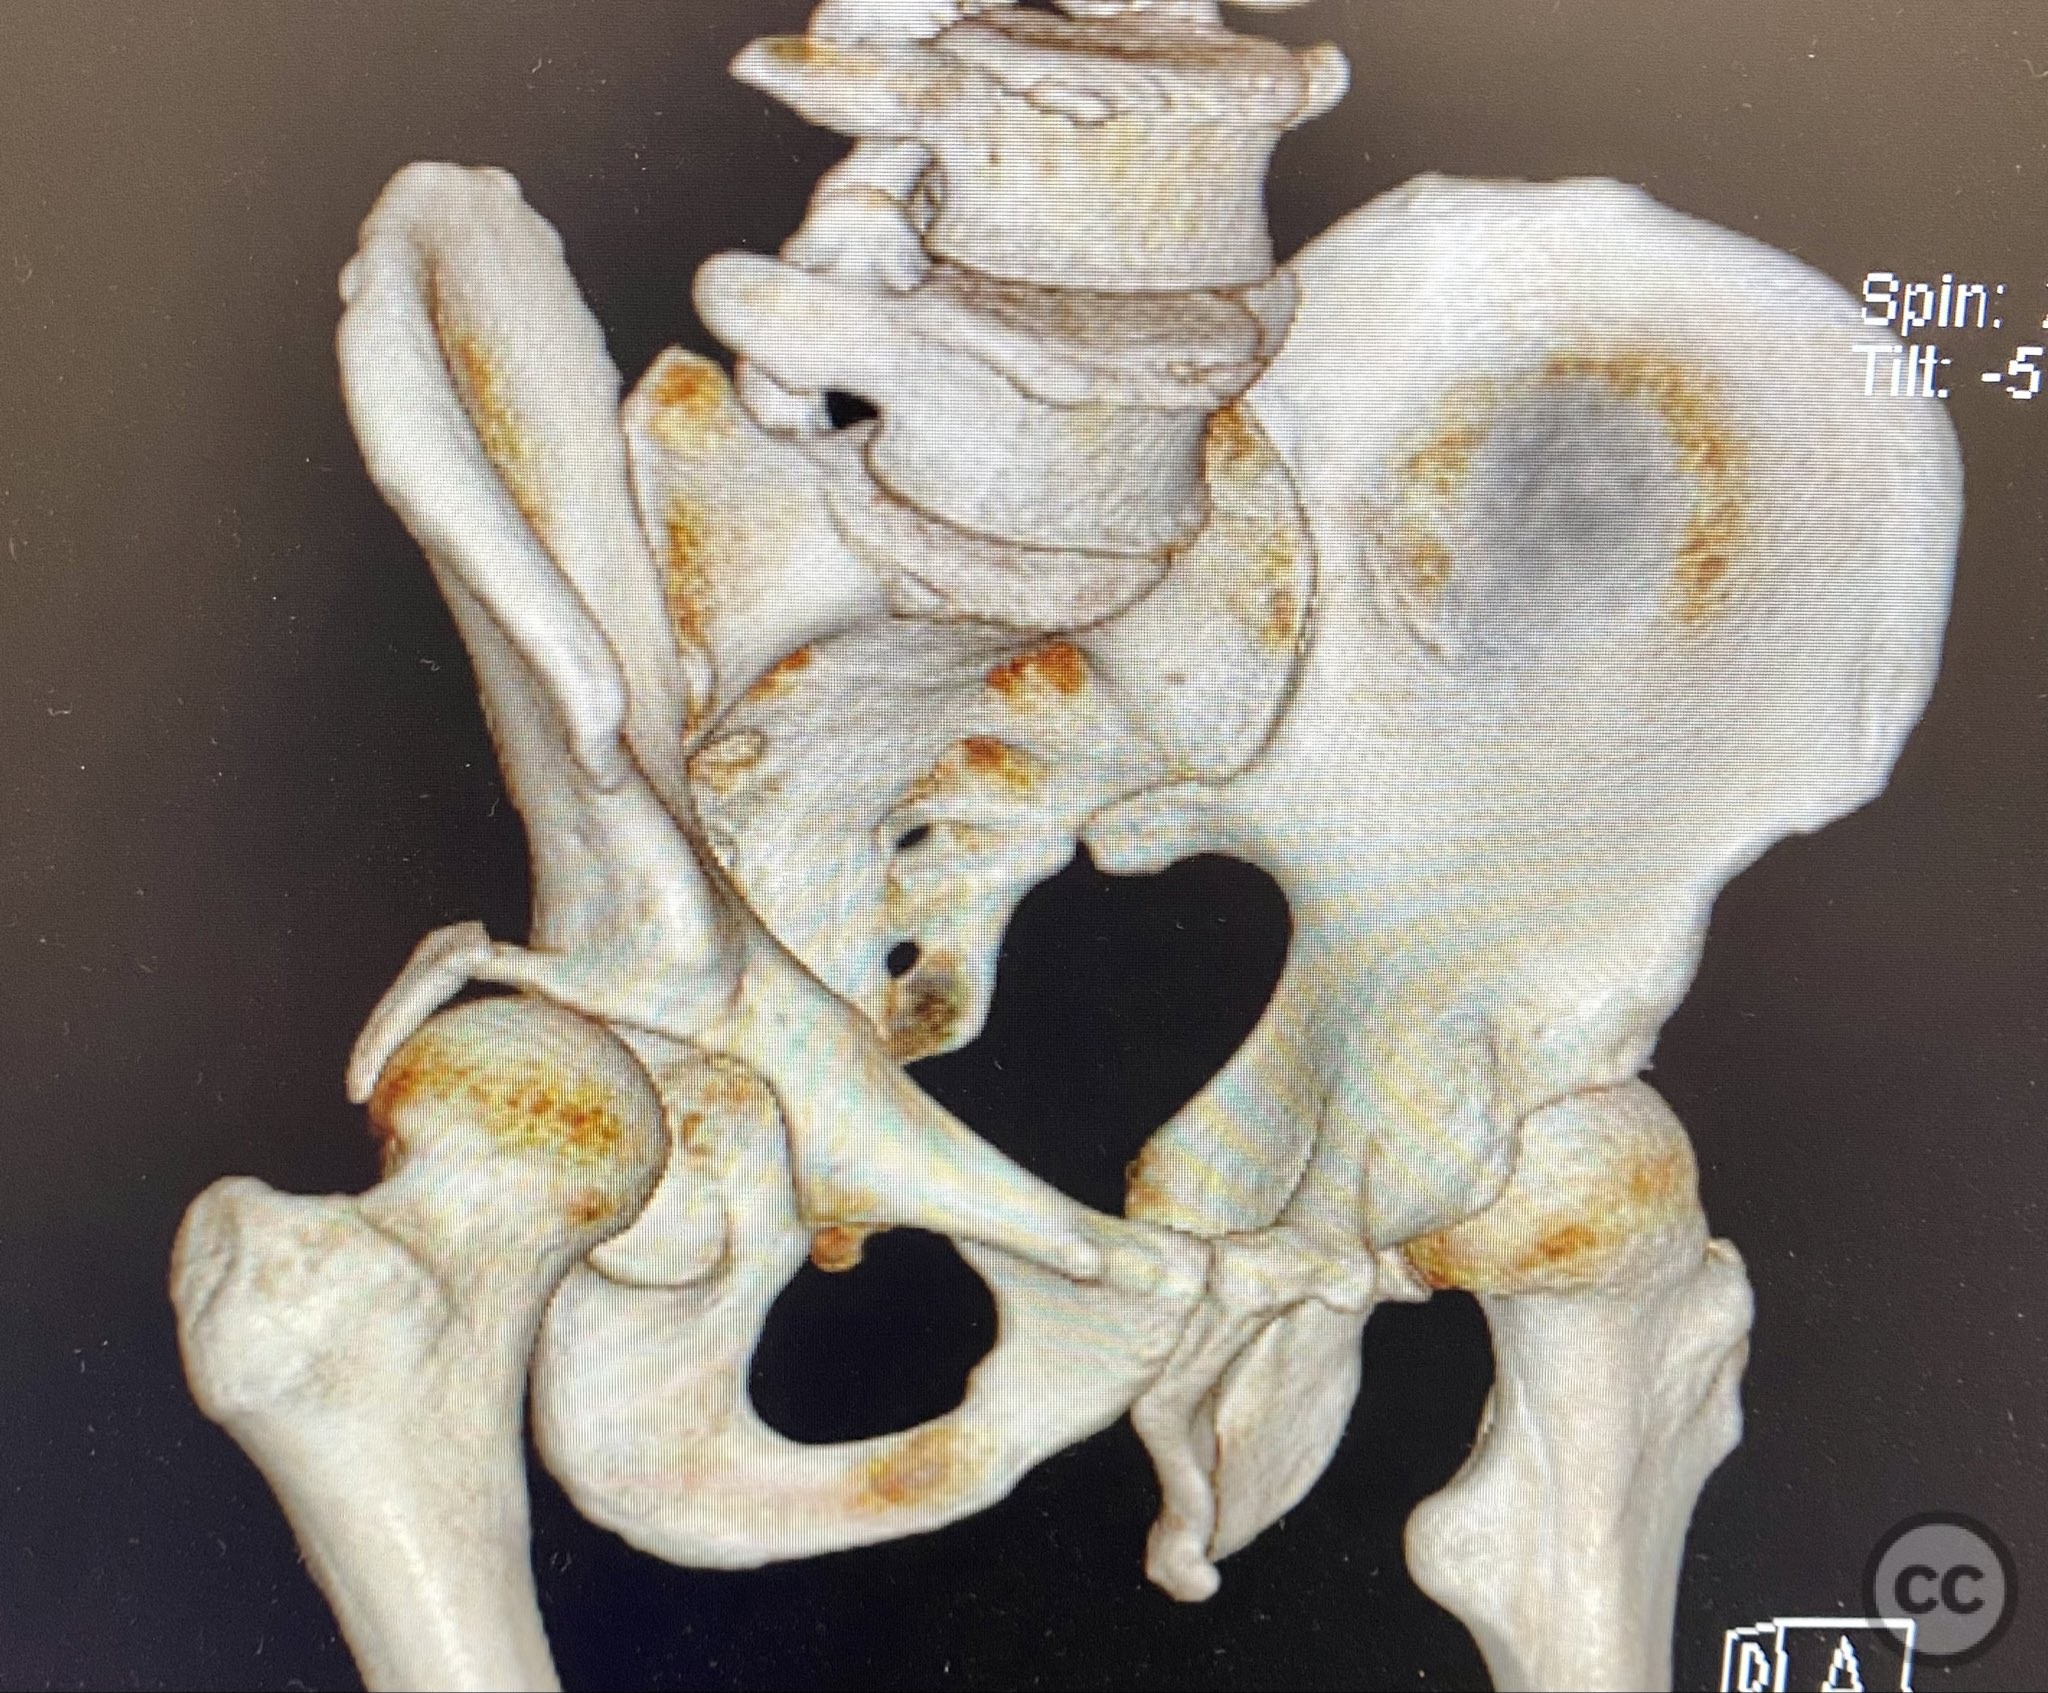

Planning remarks:  The preoperative plan included advanced imaging with CT, including 3D surface renderings, to further delineate the extent of articular impaction, wall fragment size, and comminution. The plan was for open reduction and internal fixation via a posterior Kocher-Langenbeck approach in the prone position. Elevation of impacted articular segments was planned, with structural support using autologous bone graft harvested from the greater trochanter. Fragment-specific fixation was planned with a spring hook plate for the cranial wall fragment and a reconstruction plate for the main posterior wall fragment.

The initial failed closed reduction likely resulted from interposed soft tissue or bony fragments, or inadequate sedation/muscle relaxation. Repeat reduction under improved conditions was successful prior to definitive fixation. 3D CT renderings provided enhanced visualization of impaction zones and comminution, facilitating preoperative planning for grafting and fragment-specific fixation. Intraoperatively, elevation of the impacted dome required careful manipulation to avoid further chondral injury. Use of a spring hook plate provided secure fixation of the cranial wall fragment, while the reconstruction plate supported the main wall fragment. Postoperative CT confirmed satisfactory reduction and implant positioning.